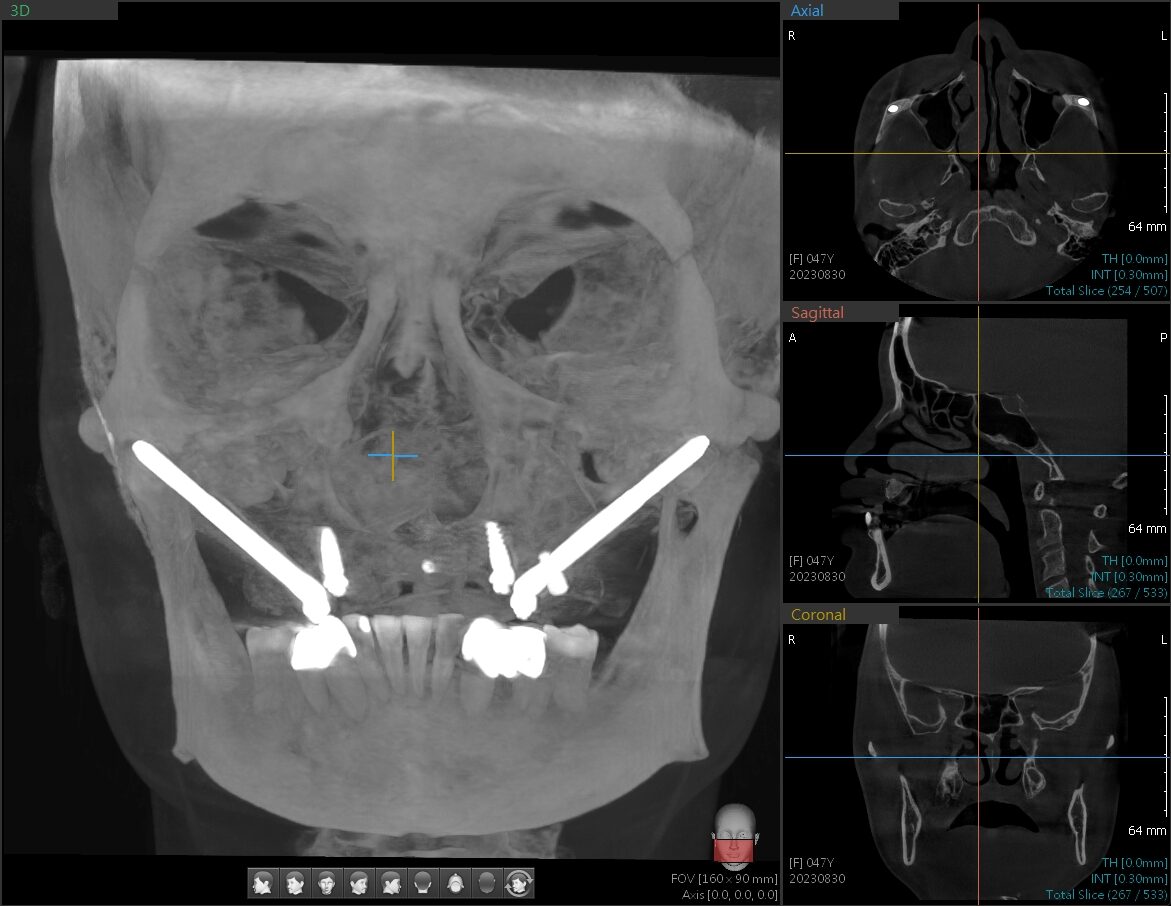

林楚喬醫師於2023年,使用2支顴骨植牙重建口腔。

技術特點: 植體長度極長(約 30mm 至 52.5mm),斜向植入人體堅硬的**顴骨(Cheekbone)**中。這讓即使完全沒有齒槽骨的患者,也能在當天或短時間內裝上固定假牙。

技術特點: 植體長度較普通植體長(約 15mm 至 20mm),植入角度約呈 45 度,穿過上顎結節鎖在翼板骨上。